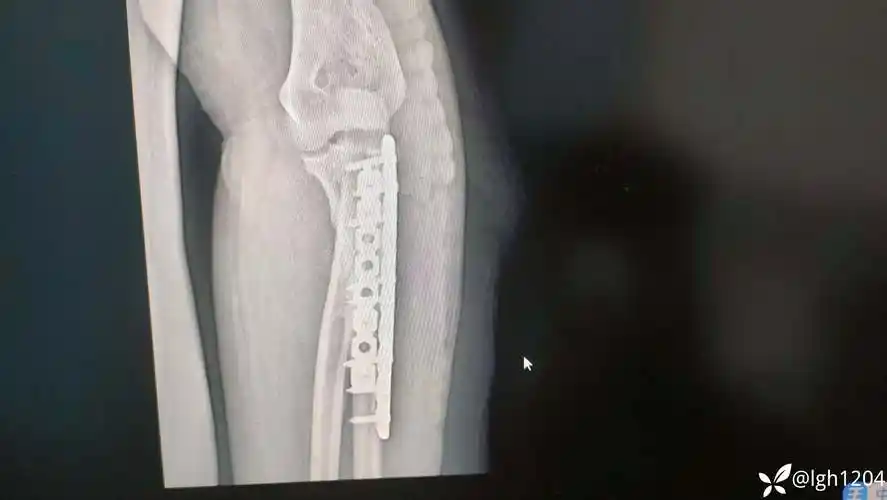

尺骨近端合并桡骨颈陈旧性骨折